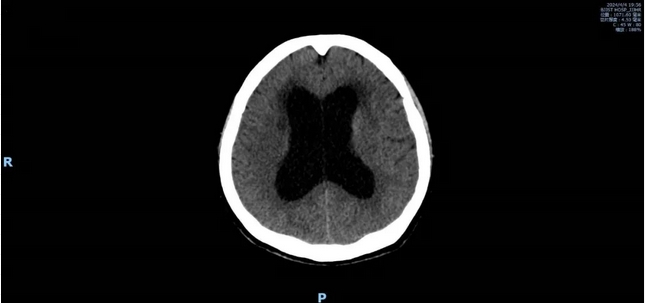

刚下飞机,黄阿姨走不稳的情况比登机前更严重了,只能坐轮椅行动,心急万分的家属立刻将她送到了北京积水潭医院回龙观院区急诊。头部CT检查显示,侧脑室第三、第四脑室扩大,生化显示肝功轻度升高,D-二聚体明显升高,存在颅内感染的可能。神经内科急诊的医生将她收治入院,做进一步的检查。

鉴于黄阿姨的症状表现,主管医生继续进行抗病毒、抗细菌、保肝及补液治疗的急诊治疗方案。在完善头部核磁检查后,结果仍显示以脑室系统扩大为主,准备完善腰椎穿刺检查。